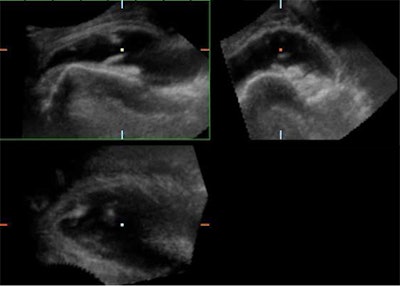

![]() |

| Biceps tendinitis associated with rotator cuff defect. The coronal plane readily demonstrates subtle tears and irregularities of the biceps tendon within an effusion. 3D reconstruction confirms the irregularities of this tendon and the large effusion is well-appreciated. Bottom right image demonstrates fluid collection and right coracobrachialis longus (CBL). |